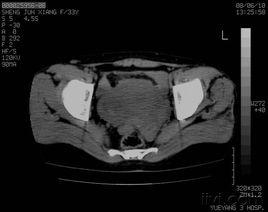

由於盆底鬆弛綜合徵缺乏特異性的症狀和體徵,又由於很多疾病都可以導致排便困難,所以正確作出盆底鬆弛綜合徵的診斷並非易事。首先要排除脊髓病變,排除結腸因素所致便秘,排除大腸腫瘤等病變,然後根據病史、症狀、體徵,做排糞造影,可見多種鬆弛病變同時存在,即可作出盆底鬆弛綜合徵的診斷。女性患者若伴有子宮脫垂,陰道寬大,壓力性尿失禁等,則強力支持本診斷。

盆底失弛緩綜合徵的主要臨床表現應當是排大便困難,即使是成形軟便也術易排出,患者會有會陰部滿脹感,肛門張不開等感覺。該病的確診主要靠肌電圖檢查和排糞造影。肌電圖檢查可見盆底多組肌肉同步反常放電。排糞造影檢查可見在用力排便時肛門直腸角不變大甚至變小。對盆底失弛緩綜合徵的治療目前尚無很好的辦法,主要還是以保守治療為主,如飲食中增加粗纖維量,多飲水。可以使用瀉劑,但不要依賴瀉劑,最好口服瀉劑和外用開塞露(每次20~40毫升),以及生理鹽水灌腸(每次500毫升)交替使用。